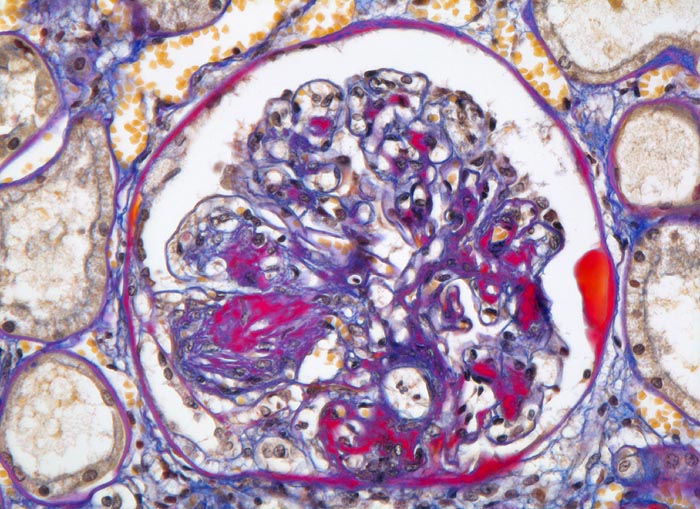

• Verbreiterung des Mesangiums mit Ausbildung von Knoten(noduläre Glomerulosklerose).

• Exsudative Läsionen: Hyaline Schlingenkappen (Proteinthromben in Glomerulumschlingen, im virtuellen Präparat nicht sichtbar) und Kapseltropfen (Proteinablagerungen im Bowman’schen Kapselraum).

• Arteriolosklerose von Vas afferens und efferens (Gefässwandhyalinose durch Ablagerung von Plasmaproteinen und Lipiden in der Gefässwand).

• Verdickte Basalmembranen der peritubulären Kapillaren.

• Verbreiterung der tubulären Basalmembran.

Im allgemeinen ist die Niere infolge von Glomerulumhypertrophie und Tubulushyperplasie vergrössert und derb, die Oberfläche ist granuliert. Bei schwerer Atherosklerose und fortgeschrittener Niereninsuffizienz kann die Niere auch normal gross oder verkleinert sein. Die Kombination von nodulärer Glomerulosklerose, hyalinen Schlingenkappen (=Proteinthromben in den Glomerulumschlingen (> 1916)) oder Kapseltropfen (> 1907) und Arteriolosklerose in Vas afferens und efferens ist beweisend für eine diabetische Nephropathie. Jede einzelne Läsion für sich genommen ist aber unspezifisch. Eine noduläre Glomerulosklerose kann auch vorkommen bei membranoproliferativer Glomerulonephritis (> 2652), Leichtkettenglomerulopathie oder Amyloidose (> 2019). Der nodulären Glomerulosklerose geht bei Diabetikern eine diffuse Glomerulosklerose (> 1906) voraus. Dabei zeigen die glomerulären Basalmembranen und das Mesangium eine progrediente gleichförmige Verbreiterung. Bei der nodulären und diffusen Glomerulosklerose handelt es sich aber wahrscheinlich um zwei pathogenetisch unterschiedliche, sich überlagernde Krankheitsbilder. Typisch bei Diabetikern ist im Unterschied zur arteriellen Hypertonie die Arteriolosklerose von Vas afferens und efferens (> 1911) und oft auch der Vasa recta. Intrarenale Arterien können eine Atherosklerose mit Atheromen zeigen. Subendotheliale Proteinablagerungen teilweise mit Verschluss der Glomerulumschlingen (Schlingenkappen) und knotige Proteinablagerungen in der Bowman'schen Kapselbasalmebran (Kapseltropfen) gehören zu den sogenannten exsudativen Läsionen (> 1919) (> 1920) der diabetischen Nephropathie und führen zu Synechien sowie zur globalen Glomerulosklerose. Gleichzeitig mit den Glomerulumveränderungen treten tubuläre Basalmembranverbreiterungen auf, später eine Tubulusatrophie und interstitielle Fibrose mit Begleitentzündung. Auch die Basalmembranen der peritubulären Kapillaren sind verdickt.